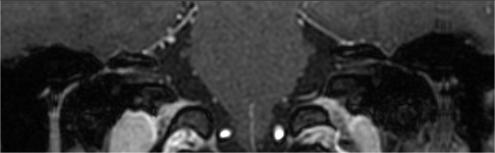

关注日前,27岁的王女士在无明显诱因的情况下突然出现右眼闭眼不全,同时伴有右面颊部麻木、口角歪斜,随后又出现右耳疼痛及发热,体温最高达到38.1℃,外敷膏药及静滴消炎药治疗后,发热症状得以缓解,但其它症状并无明显缓解。王女士遂来西安市中心医院就诊,医师为王女士做了相关专科检查,发现她的右耳廓及外耳道皮肤充血肿胀,牵拉感到疼痛,局部见散在疱疹。此外,王女士右眼闭眼时露白,右侧额纹及鼻唇沟变浅,鼓腮时右侧口角漏气,口角歪斜。结合王女士的临床症状,即右耳部疼痛、疱疹,并伴有右侧周围性面瘫,耳鼻喉科医生初步诊断为亨特综合征。之后,安排王女士又进行了面神经MRI增强检查及曲面重建,图像显示右侧面神经内听道段、乳突段增粗且强化明显,右侧耳廓肿胀并明显强化,王女士的疾病最终确诊为亨特综合征。

(注:白色箭头所指为右侧面神经内听道段、

乳突段增粗且强化明显)

MRI增强扫描技术是诊断亨特综合征的有效方法之一,多表现为患侧面神经节段性异常明显强化,强化程度明显高于健侧正常面神经。但面神经本身走行迂曲,主干直径较小,常规影像检查无法将面神经全程完整显示在一副图像上,发现病灶也相对较困难。面神经MRI增强扫描曲面重建技术可以将不同层面的结构重建在同一层面上,以显示面神经全貌及走形,且对病灶的显示也较清晰,在亨特综合征诊断中发挥了较好的效果。西安市中心医院放射科配备Philips Ingenia 3.0T MRI及GE HDXT 1.5T MRI扫描仪,自2016年开展面神经磁共振成像及曲面重建技术,通过多平面重建图像,不仅可以显示面神经本身全貌,且对于亨特综合征的成像,可以直观显示面神经病变节段,明确范围,便于及时发现患者的病因,有助于临床积极诊断和治疗。